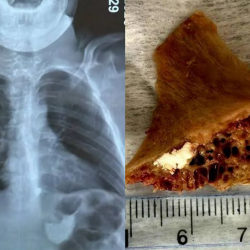

Бишкекте 15 жаштагы өспүрүм сөөк жутуп алып, кызыл өңгөчүнө тыгылып калган. Бул тууралуу Бишкек шаардык медициналык тез жардам балдар клиникалык ооруканасынан билдиришти.

Маалыматка ылайык, бала 4 сантиметр өлчөмдөгү сөөктү жутуп алган. Шаардагы эки ооруканада сөөктү чыгара алышпагандыктан, бала Бишкек шаардык медициналык тез жардам балдар клиникалык ооруканасына жеткирилген.

"Дарыгерлер ыкчам түрдө операция жасап, тыгылып калган сөөктү ийгиликтүү алып чыгышты. Оор абалда келген балага дароо керектүү медициналык жардам көрсөтүлүп, операцияга жасалды", - деп белгилешти ооруканадан.

Учурда өспүрүмдүн абалы туруктуу экени айтылды.